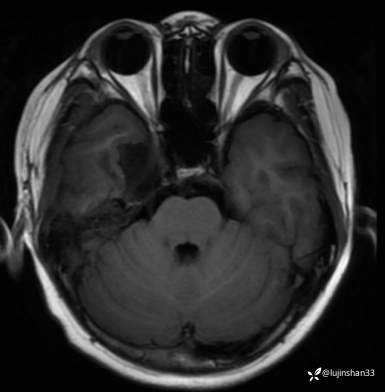

术后

【临床诊断】:颅底占位

【治疗经过及结果】:显微镜下颅中窝入路右侧颅底病变切除术,术后恢复良好。